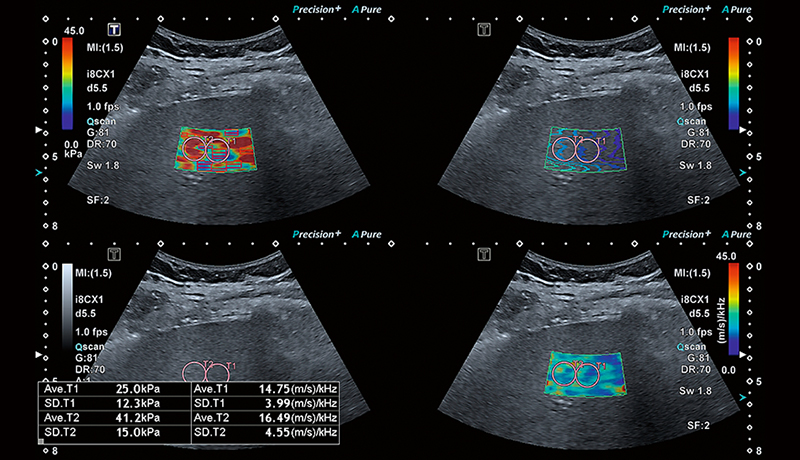

Унікальний режим чотирьохканального перегляду Canon дозволяє одночасно порівняти швидкість, еластичність, поширення та дисперсію зсувної хвилі для більш повної та надійної оцінки стану печінки.

Залежно від ступеня фіброзу, паренхіма печінки демонструє підвищену віскоelasticity (в’язкопружність). Клініцисти досліджують жорсткість печінки як один із показників для діагностики фіброзу або цирозу печінки. Жорсткість печінки можна виміряти за допомогою еластографії зсувної хвилі (SWE).

Розумні карти допомагають візуалізувати поширення зсувної хвилі в режимі реального часу. Унікальна карта поширення від Canon – це потужний та інтуїтивно зрозумілий інструмент для візуальної оцінки якості еластограми.